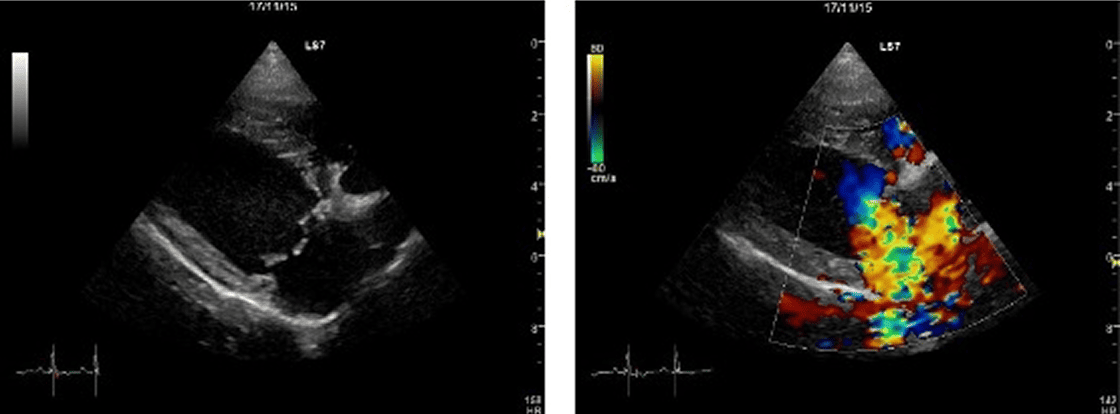

僧帽弁形成術術前

僧帽弁形成術前の心臓超音波画像(右傍胸骨長軸四腔断面像)。Carpentier's functional classification typeⅡの特徴である弁尖の逸脱が前尖・後尖共に見られる。またカラードプラ画像では重度の僧帽弁逆流がみられる。